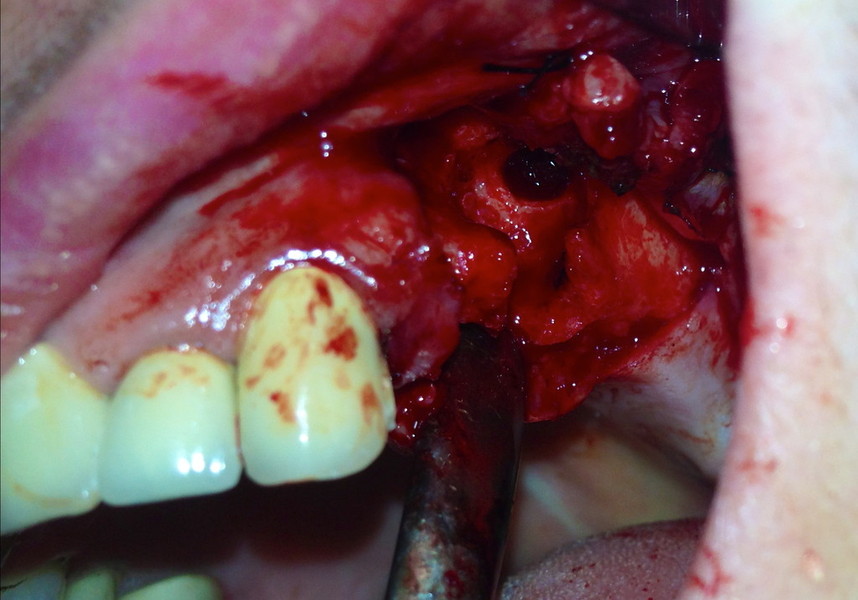

rigenerazione grave difetto parodontale a carico una intera emiarcata